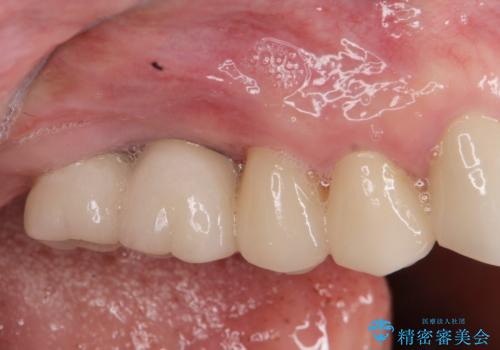

[ 破折し大きく吸収した歯槽骨 ] 他院では難しいと言われたインプラント治療

![[ 破折し大きく吸収した歯槽骨 ] 他院では難しいと言われたインプラント治療の症例 治療前](https://seimitsushinbi.jp/wp/wp-content/uploads/2024/10/073ce5e06775df372887a513b05b34d0-500x350.jpg?v=1729760111)

![[ 破折し大きく吸収した歯槽骨 ] 他院では難しいと言われたインプラント治療の症例 治療後](https://seimitsushinbi.jp/wp/wp-content/uploads/2024/10/7e00d9287463e80cbc3d4b87784b3d86-500x350.jpg?v=1729760167)